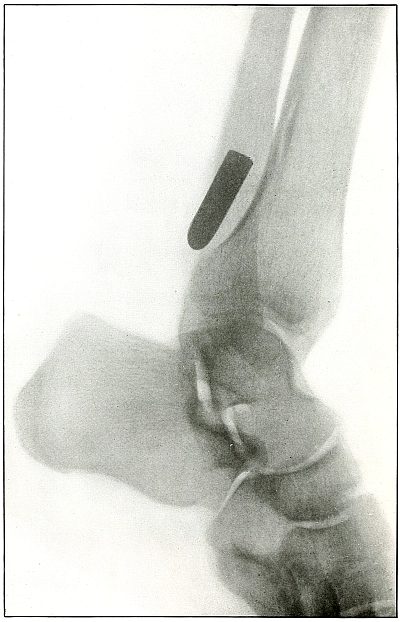

Gunshot fracture, ankle |

154 |